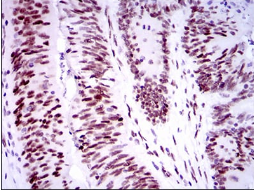

| AC3707 | TP53BP1 Mouse Monoclonal antibody[6B3E1] | 100ug | $367 | 10days |

| AC3707 | TP53BP1 Mouse Monoclonal antibody[6B3E1] | 200ug | $660.6 | 10days |